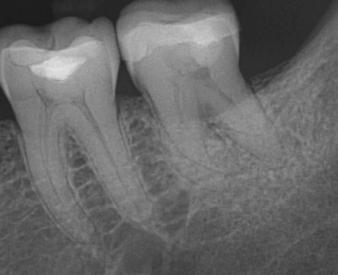

Radiographs of a 61-year-old female who presented with pulp necrosis and asymptomatic apical periodontitis. Dr. Wiseman performed minimal instrumentation in this case due to the dilacerated and calcified canals. The mesial canal has a 45 degree curvature in the apical 1/3 of the root. The GentleWave procedure was completed. Radiographs viewed are the preoperative 2D and 3D images and the postoperative image

Radiographs of an 80-year-old male who presented with pulp necrosis and asymptomatic apical periodontitis. Dr. Wiseman performed minimal instrumentation in this case due to the dilacerated and calcified canals. The mesial canal has a 45 degree curvature in the apical 1/3 of the root. The GentleWave procedure was completed. Radiographs viewed are the preoperative 2D and 3D images and the postoperative image